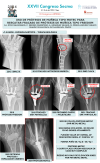

Inestabilidad articulación metacarpofalángica del 5º dedo postraumática.

SERGIO VALLE LÓPEZ, Inés De Blas Sanz, Jesús Diez Rodríguez, Ignacio García Cepeda